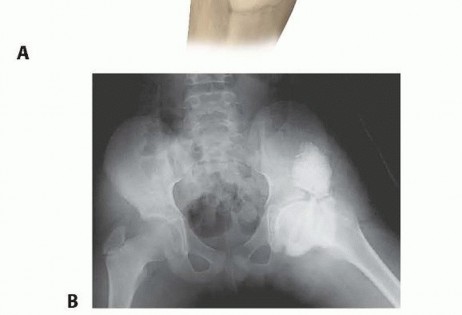

After the infarction, the child is usually asymptomatic, but a subchondral fracture subsequently develops in the necrotic bone and the hip becomes irritable22 (

FIG 2

).

| ### FIG 2 • Computed tomography of the hip of a patient with Perthes disease showing necrotic bone in the epiphysis and a subchondral fracture. Group | Loss of Height of the Lateral Column of the Femoral Epiphysis | Prognosis |